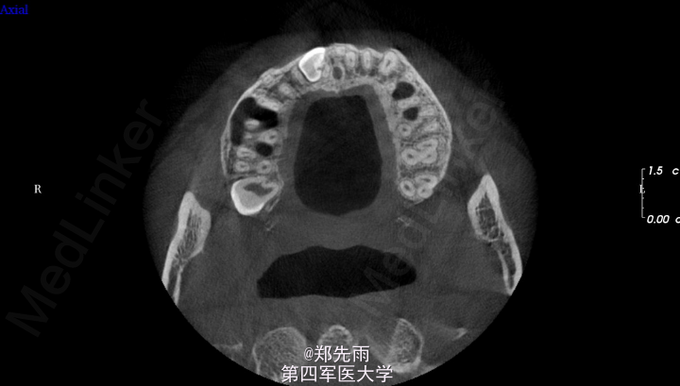

正畸要求拔除埋伏牙转诊。 正畸要求拔除上前牙区埋伏13、多生牙以及24、34、44、18、28、38.

13先天性埋伏阻生,前鼻棘下方埋伏牙,行CBCT检查提示均位于唇侧,但CBCT提示双侧上颌后牙牙根不同程度位于上颌窦内。

诊断:13埋伏阻生,上颌埋伏多生牙。 处理:住院拔除上颌埋伏牙,分次拔除正畸减数牙。与患者术前充分沟通上颌窦穿孔、上颌窦瘘的可能。